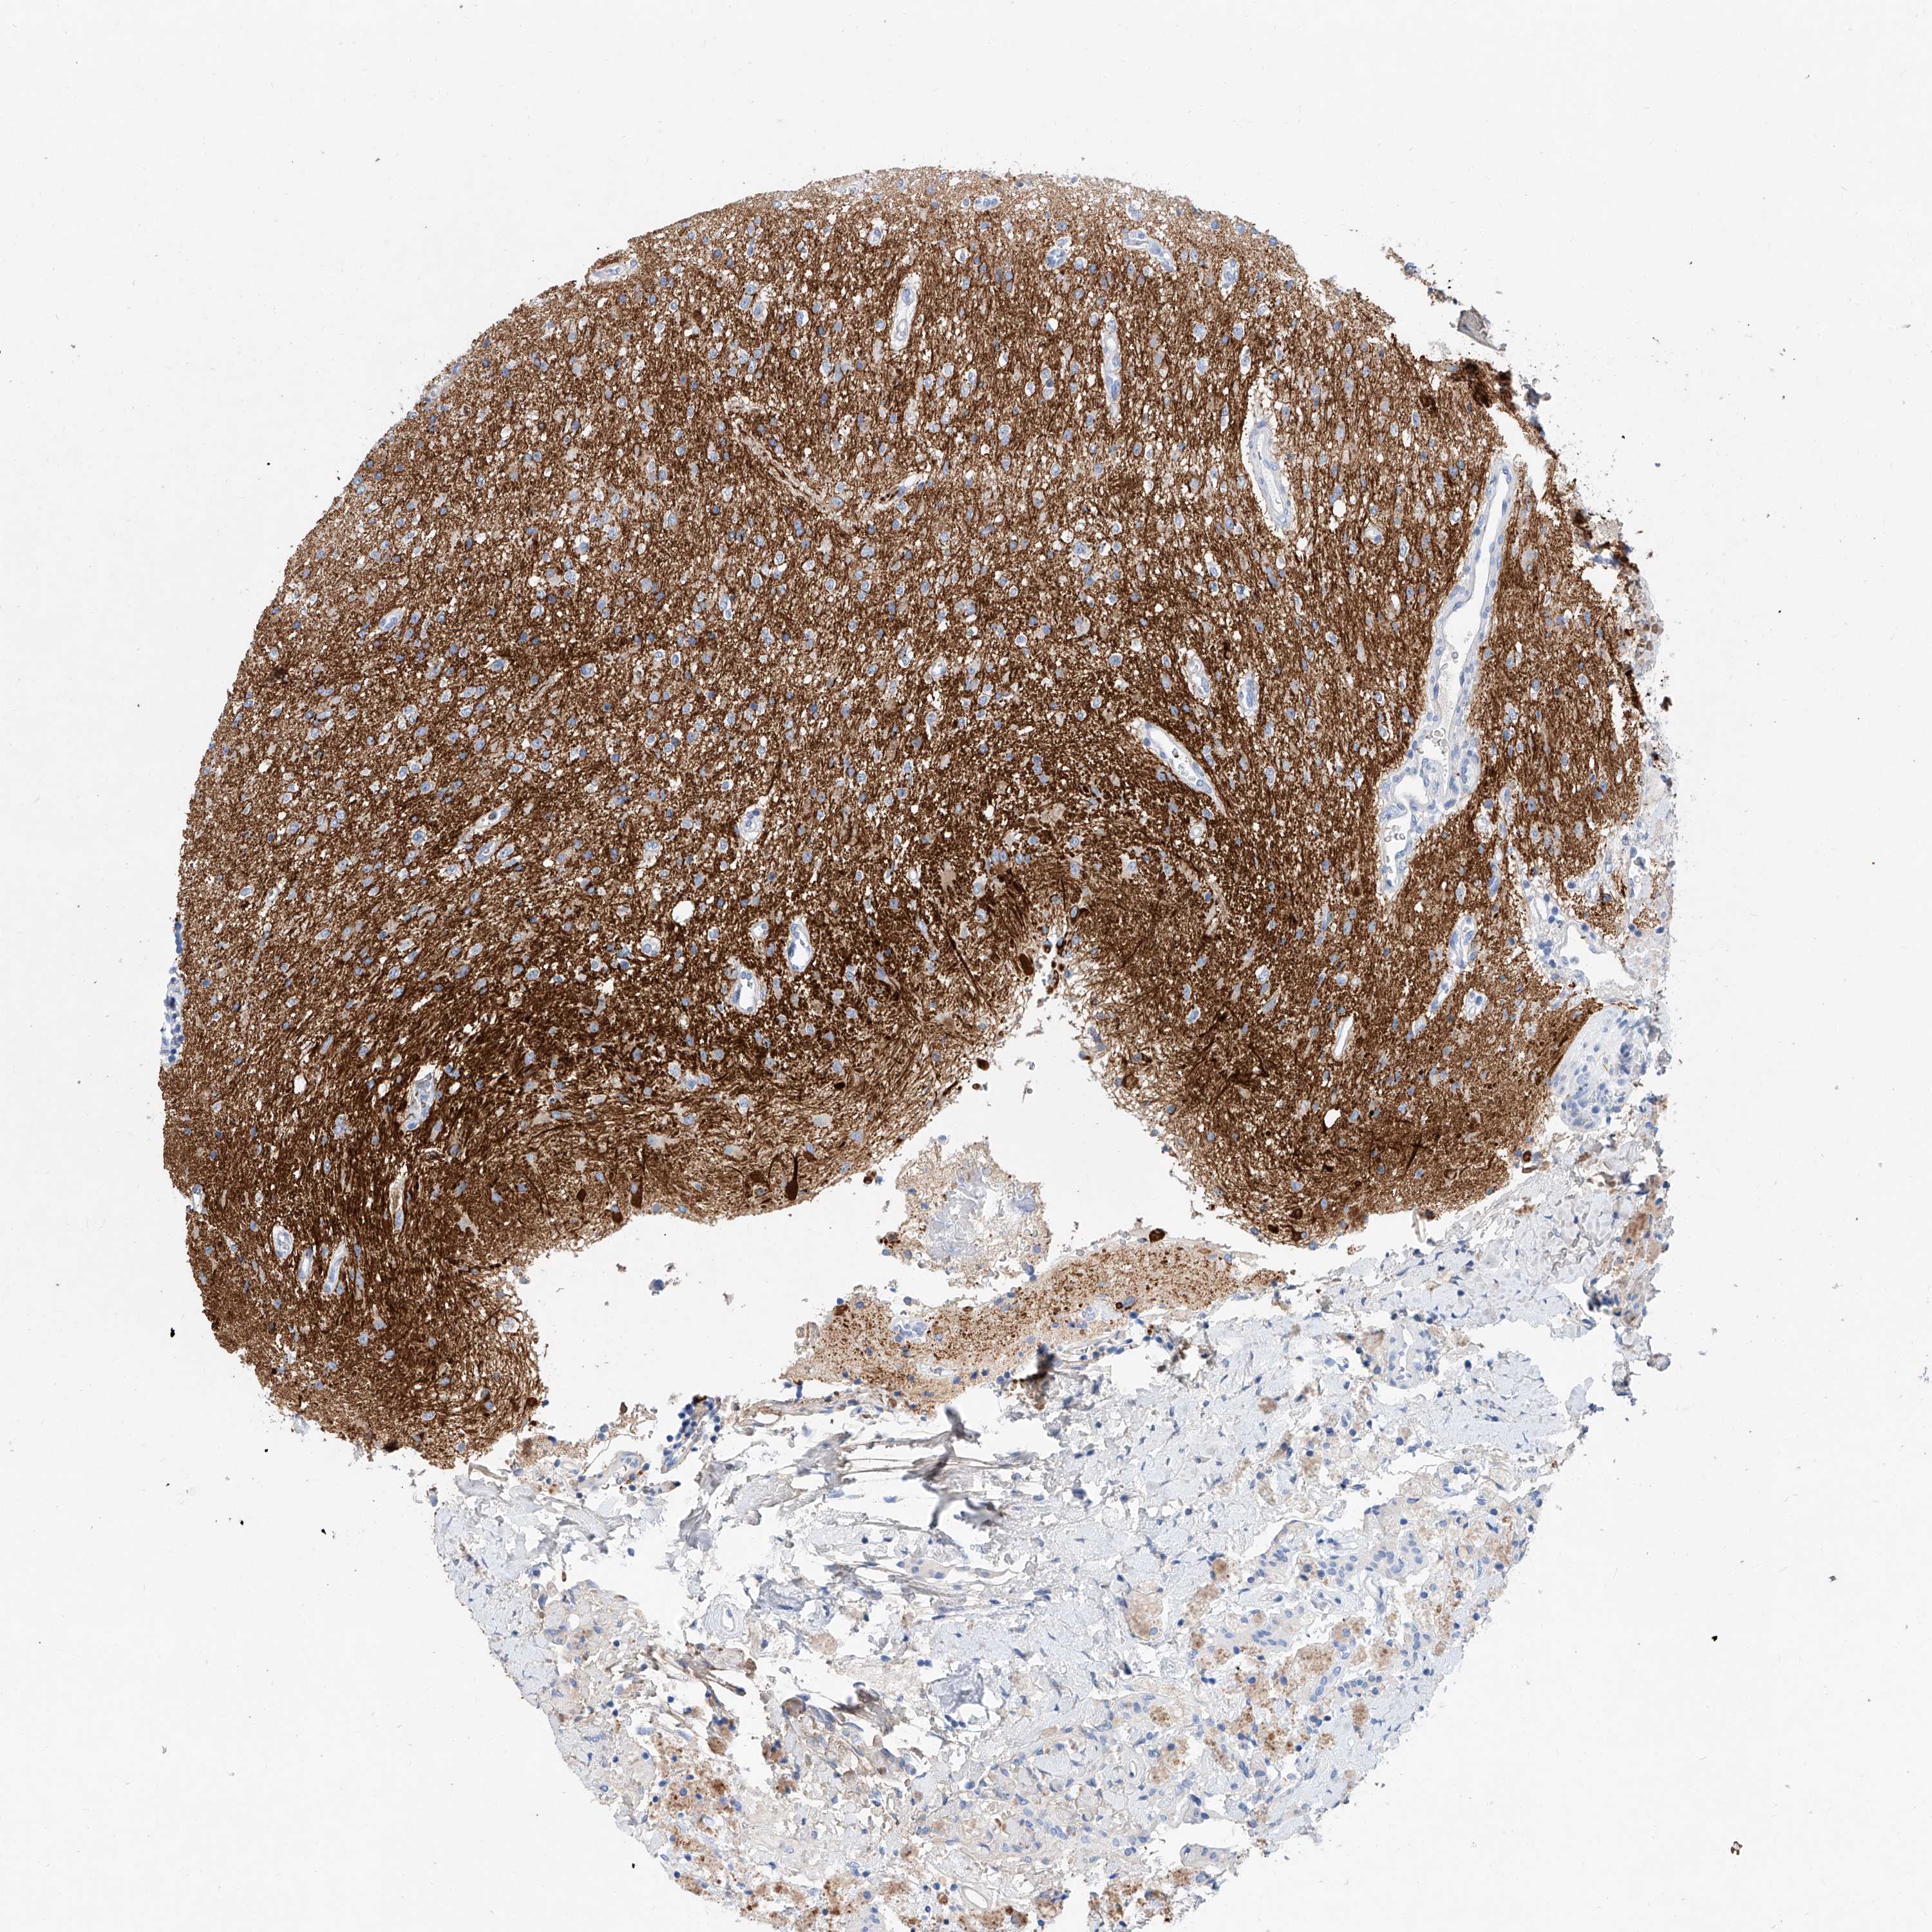

GLIOMA - Protein expressioni

A mouse-over function shows sample information and annotation data. Click on an image to view it in a full screen mode. Samples can be filtered based on level of antibody staining by selecting one or several of the following categories: high, medium, low and not detected. The assay and annotation is described here.

Note that samples used for immunohistochemistry by the Human Protein Atlas do not correspond to samples in the TCGA dataset.

Antibody stainingi

Antibody staining in the annotated cell types in the current human tissue is reported as not detected, low, medium, or high, based on conventional immunohistochemistry profiling in selected tissues. This score is based on the combination of the staining intensity and fraction of stained cells.

Each image is clickable and will lead to virtual microscopy that enables deeper exploration of all samples and also displays staining intensity scores, fraction scores and subcellular localization as well as patient and tissue information for each sample.

Antibody HPA030781

Staining

High

Medium

Low

Not detected

Intensity

Strong

Moderate

Weak

Negative

Quantity

>75%

75%-25%

<25%

None

Location

Nuclear

Cytoplasmic/membranous

Cytoplasmic/membranous,nuclear

Glioma, malignant, High grade

Glioma, malignant, Low grade

Glioblastoma, NOS